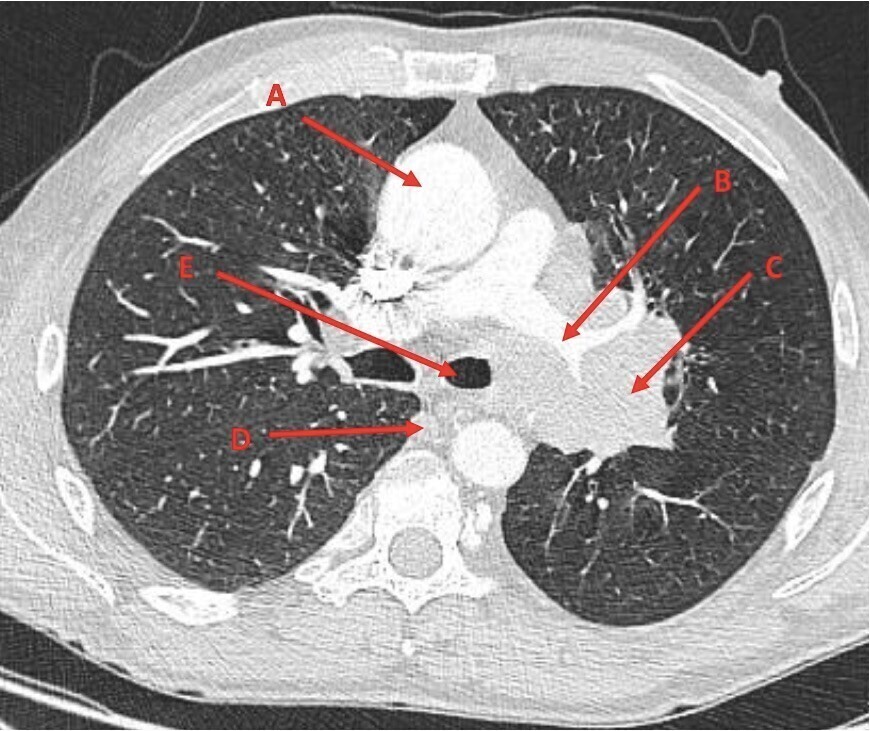

Vous réalisez le scanner thoracique suivant.

Question 9 - Indiquez les éléments correspondant à la légende :

Sur le scanner les lettres correspondent à :

– A : aorte ascendante ;

– B : artère pulmonaire gauche ;

– C : masse tumorale ;

– D : grande veine azygos ;

– E : bronche souche gauche.